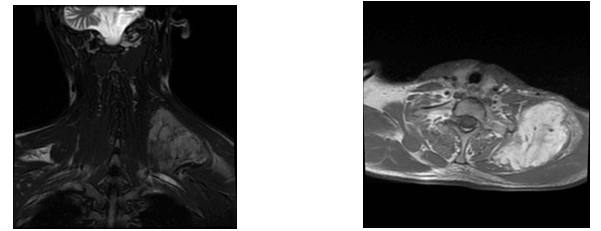

Under general anesthesia, a mass extending to the scapula was excised in two parts while preserving the phrenic nerve and brachial plexus (Figure 2). The larger mass measured 9x6x4.5 cm, and the smaller 8x4.5x4.5 cm.